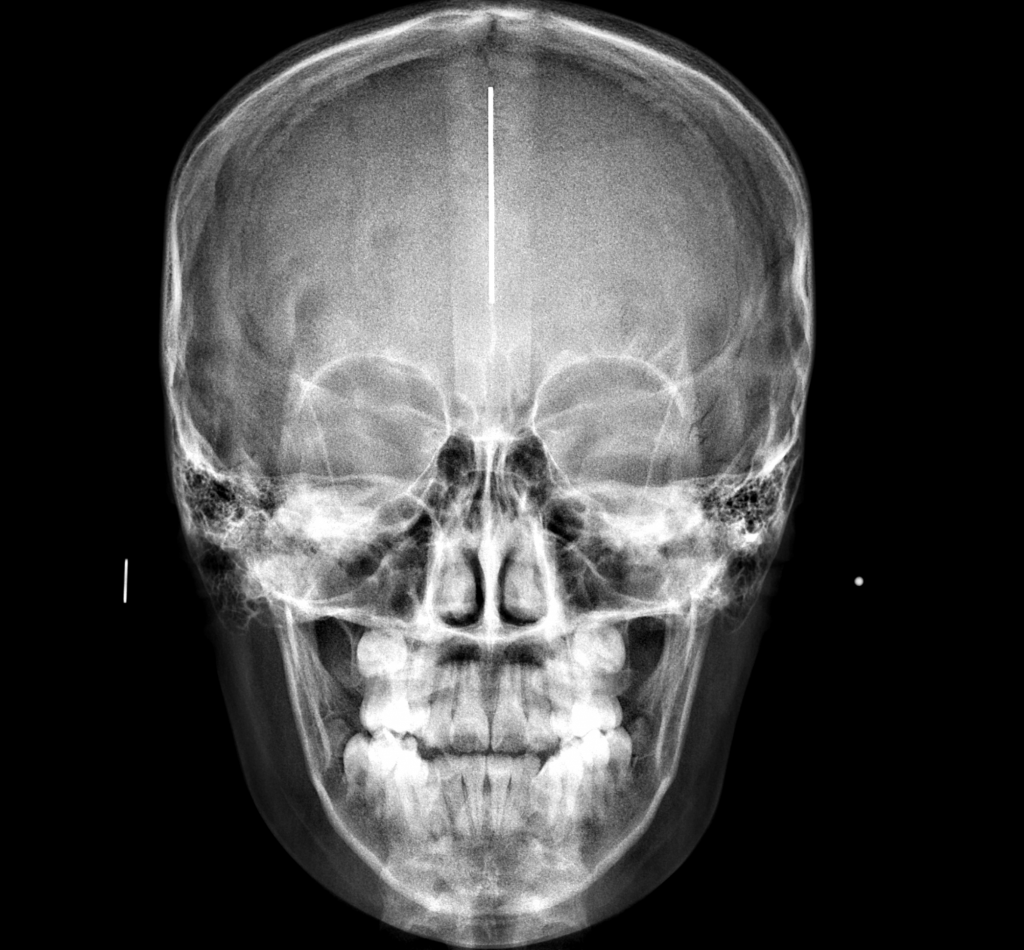

RADIOGRAFÍA Y TOMOGRAFÍA CONE BEAM ODONTOLÓGICA

CRYT Centro Radiológico y Tomográfico Odontológico / Dental en Salta

- Radiología